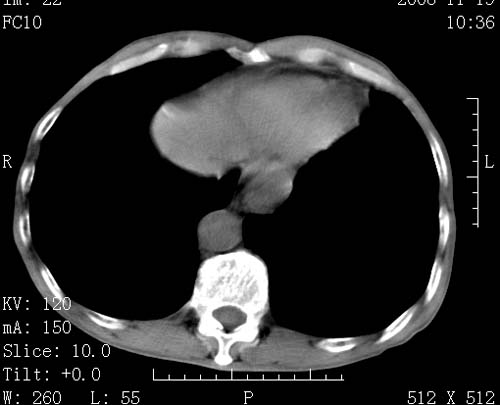

标题: CT16691:m 67 胃镜确诊食管下段及贲门癌 [打印本页]

标题: CT16691:m 67 胃镜确诊食管下段及贲门癌

术前查体,双肺部结节是转移?结核?请点评

转移 隆突下淋巴结亦肿大

首先考虑转移,纵隔内淋巴结亦肿大;

1)符合食管癌表现。2)两肺及纵隔淋巴结多发性转移瘤。3)左肺上叶舌段及两肺下叶炎症感染。

食管癌伴双肺转移,评述:肺部毛细血管网丰富,全身血液均快速流经肺部,癌细胞容易过滤定植,形成转移瘤,影象特点为以毛细血管末梢为中心的结节灶,边缘光滑锐利,少见有中心空洞着,不同来源的转移瘤可有各自特点,如甲状腺癌为双肺弥漫性微结节,本例有原发灶,双肺影象灶典型,左肺舌段条带状网格样伴胸膜天幕征,可视为癌性淋巴管炎。